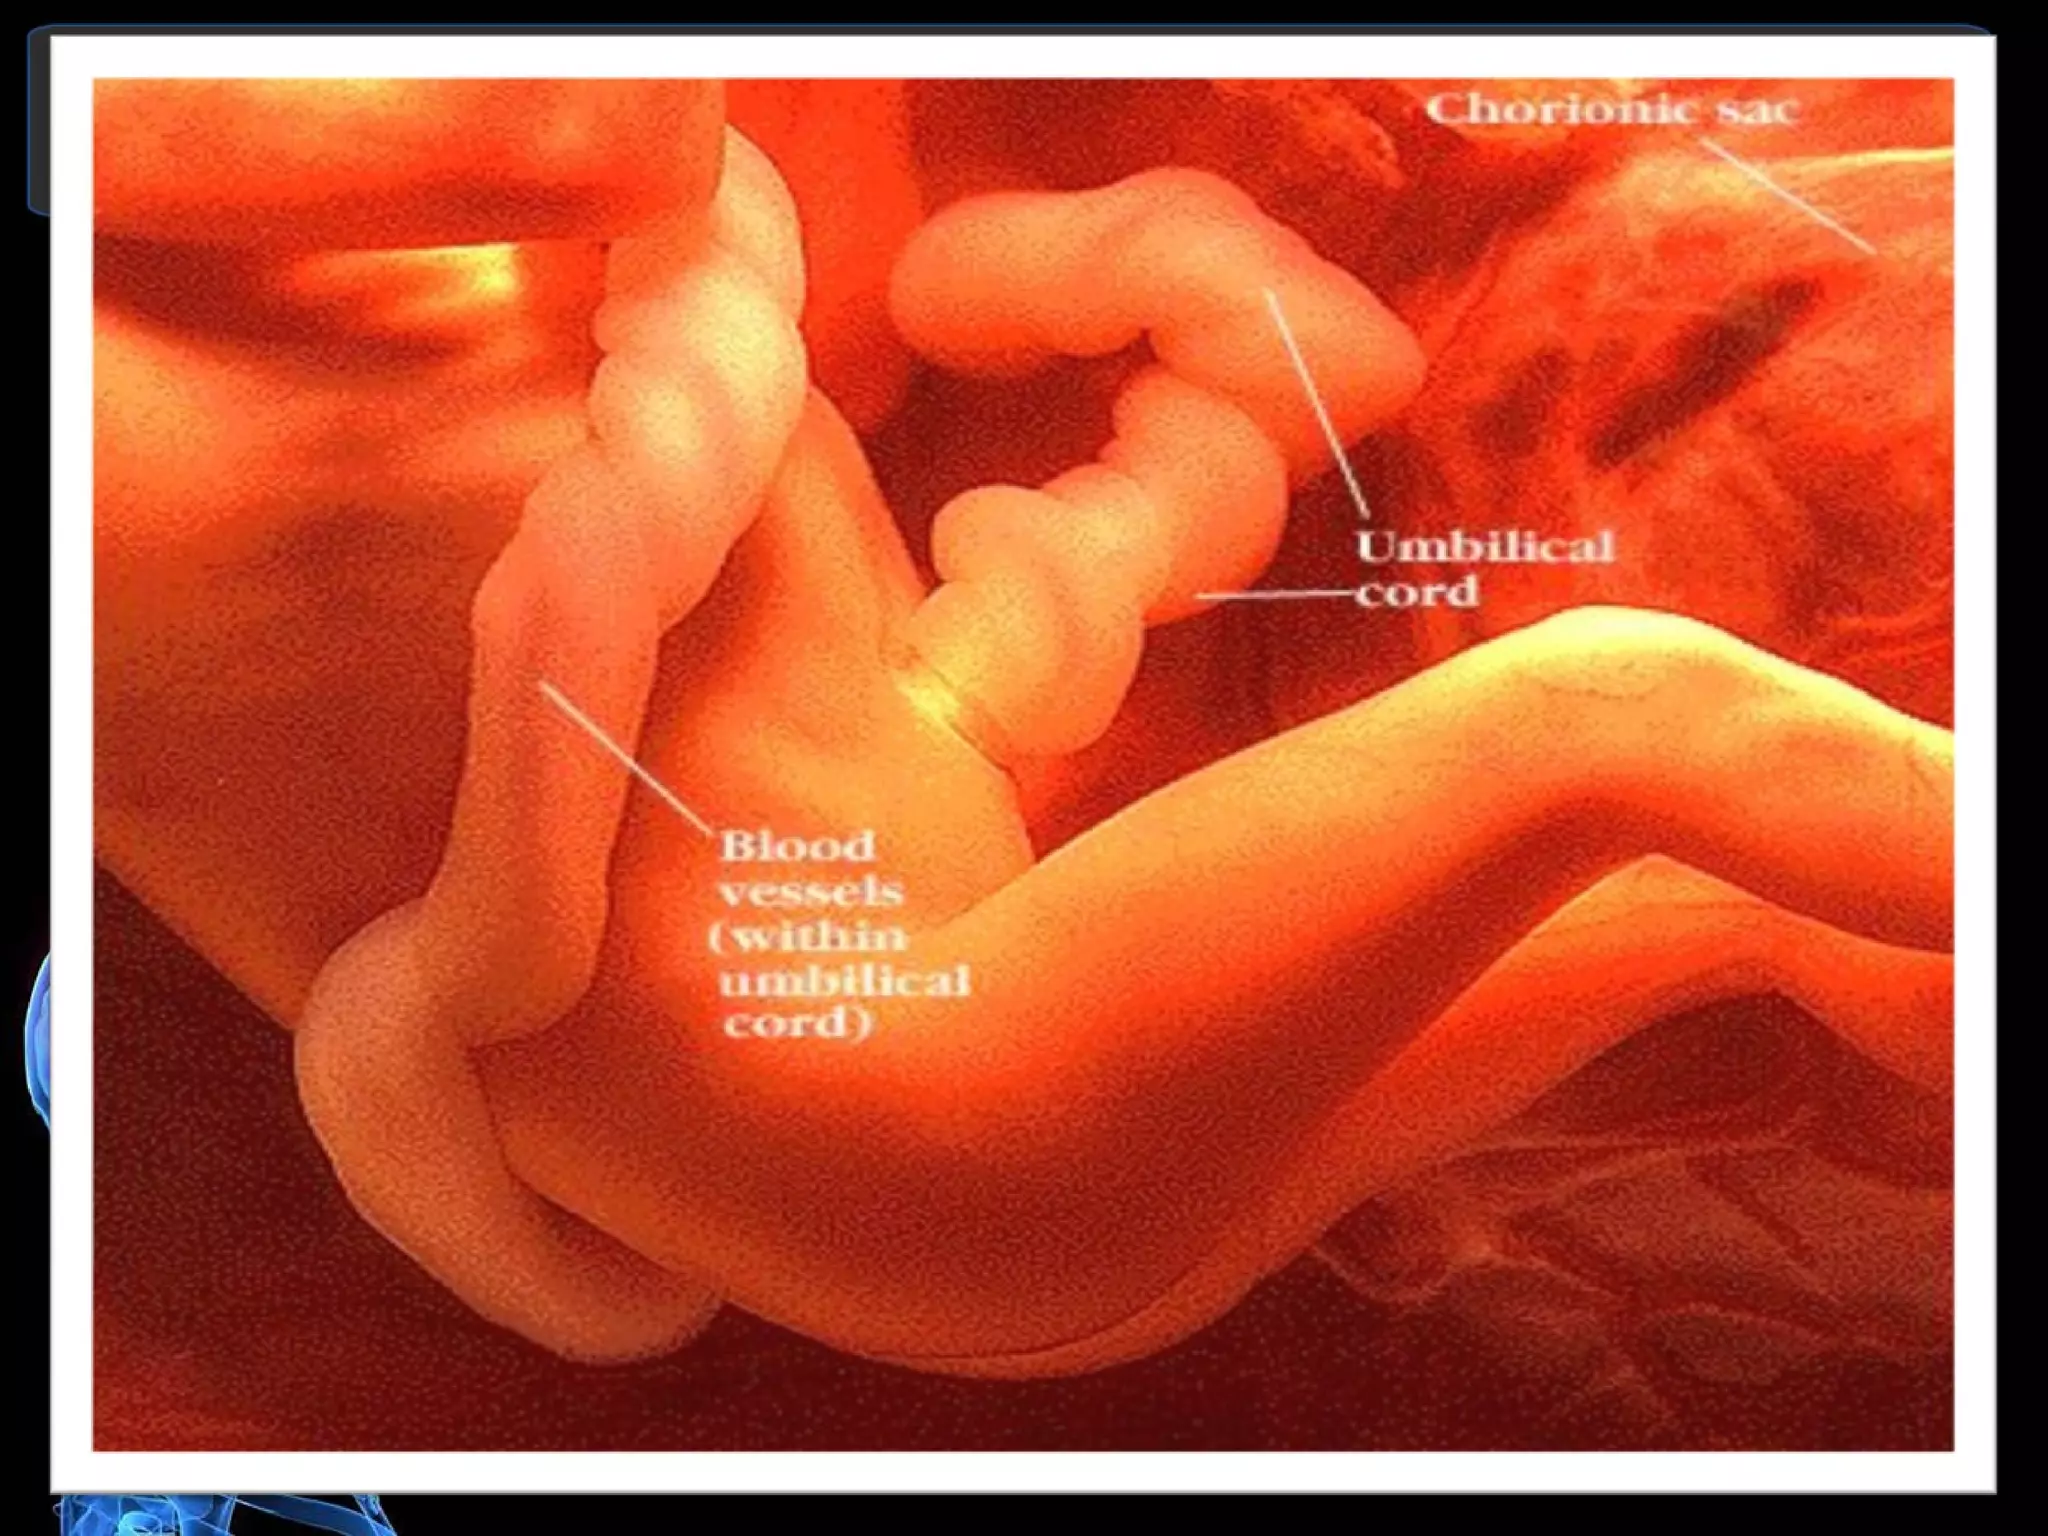

U m b i  l i c a l  C o r d It main function is to carry oxygen and nutrients from the placenta to the fetus and return un-oxygenated blood and fetal waste product to the placenta. BLOOD VESSELS: 2 arteries, 1 vein LENGHT: is about 50 to 55 cm long. It appears dull white moist and covered by the amnion. Whartons Jelly  is a gelatinous substance found inside the cord. CORD INSERTION: Central Insertion Lateral Insertion Velamentous when the chorioamniotic membrane is inserted in the membrane 5 to 10 cm away from the edge of the placenta Battledore cord id inserted at the edge of the placenta

U m bi l i c a l C o r d It main function is to carry oxygen and nutrients from the placenta to the fetus and return un-oxygenated blood and fetal waste product to the placenta. BLOOD VESSELS: 2 arteries, 1 vein LENGHT: is about 50 to 55 cm long. It appears dull white moist and covered by the amnion. Whartons Jelly is a gelatinous substance found inside the cord. CORD INSERTION: Central Insertion Lateral Insertion Velamentous when the chorioamniotic membrane is inserted in the membrane 5 to 10 cm away from the edge of the placenta Battledore cord id inserted at the edge of the placenta

Fertilization,Implantation,Fetal Development During the 11 th  to 12 th  day when implantation is achieved. The tropoblast layer of the blastocyst begins to mature rapidly. That bring the development of a fingers or probes that reach out from a single layer of cell known as chorionic villi

Fertilization,Implantation,Fetal Development Duringthe 11 th to 12 th day when implantation is achieved. The tropoblast layer of the blastocyst begins to mature rapidly. That bring the development of a fingers or probes that reach out from a single layer of cell known as chorionic villi